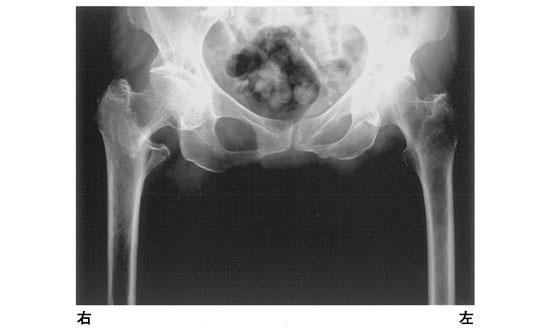

13

理学療法士実地問題 -

第54回 午前

重要度:標準

82歳の女性。転倒して右股関節痛を訴えた。エックス線写真を示す。疑うべき疾患はどれか。

1

股関節脱臼

2

坐骨骨折

3

大腿骨近位部骨折

4

恥骨結合離開

5

恥骨骨折